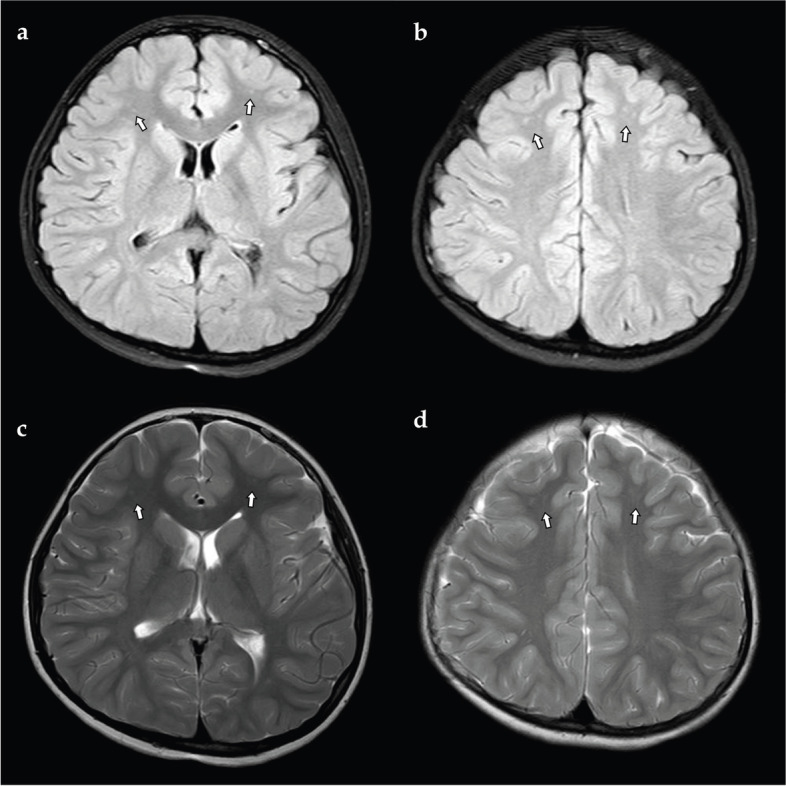

Case presentation: An 8-year-old girl who had generalized tonic-clonic seizures was diagnosed with RS induced by micturition based on the clinical manifestation and EEG recordings. We also reviewed the clinical and EEG characteristics of RS induced by micturition in literature by searching the databases of PubMed and MEDLINE using keywords "micturition reflex seizure", "reflex seizure induced by micturition", and "micturition induced seizure" by January 2022. We speculate that the mechanism of micturition-induced RS may involve excessive neuronal excitation in regions that participate in micturition.